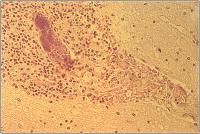

Abbildung

Septischer Embolus

Abbildung 2: Septischer Embolus mit kollateraler Entzündung und frischem Blutaustritt. H. & E., x40